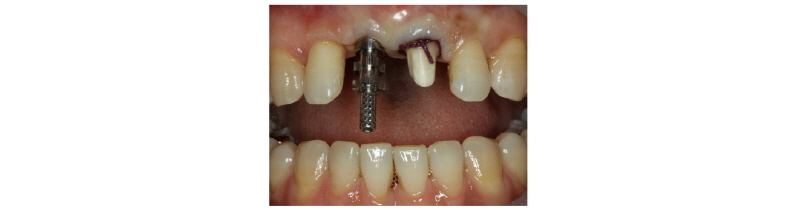

A 39-year-old male patient visited to the KyungHee University Dental Hospital with periapical abscess in the right maxillary central incisor. After clinical and radiographic examination, the tooth was planned to be extracted. The patient didn’t want to prepare the additional adjacent teeth. The right maxillary central incisor was planned to restore implant restoration and the left maxillary central incisor decided to proceed re-endodontic treatment and crown restoration (Fig. 1). Because of relatively young age of the patient, there was a lot of interest in esthetic results. Therefore, we planned to make provisional implant restoration and make a definitive prosthesis duplicating the emergence profile of the provisional restoration, and planned to use zirconia abutment when restoring the definitive prosthesis. First, preparation of maxillary left central incisor was done and maxillary right central incisor was extracted and cantilever provisional restoration was restored (Fig. 2, 3). Re-endodontic treatment of maxillary left central incisor was also progressed. After 3 months healing periods, implant placement was planned under evaluation of cone beam computed tomography scan with radiographic stent (Fig. 4). Implant placement was guided by surgical stent with bone graft (Bio-oss, Geistlich Pharma AG, Wolhusen, Switzerland) (Fig. 5, 6) and there were no systemic diseases would become problematic for implant surgery. Clinical and radiographic evaluation neither described any obvious active infection. Internal submerged type implant (4.0 mm×12.0 mm Implantium, Dentium, Korea) was placed and healing abutment was tightened. After surgery, provisional restoration was modified (Fig. 7). 3 months after implant surgery, fixture level impression was taken using pick-up impression coping (DPU 40 15 HL, Dentium, Korea) for provisional restoration (Fig. 8). Then, provisional crown with plastic provisional abutment (RAB 45 20 PHL, Dentium, Korea) was set for gingival molding (Fig. 9). During 3 weeks of provisional restoration period, the patient was satisfied with the function and the appearance of the provisional restoration. To transfer the emergence profile of provisional restoration, transfer technique was used with polyvinyl-siloxane impression material (Silagum, light body and putty, GmbH, Germany) (Fig. 10) and impression coping was modified. The final fixture level impression was taken using polyvinyl-siloxane impression material (Express light body and regular body, 3M ESPE, St Paul, MN, USA) after connection of modified pick-up impression coping (Fig. 11). A CAD/CAM zirconia abutment was milled and abutment adapted. Resin material (Pattern Resin LS; GC, America) and wooden sticks were used for delivery to laboratory of anterior teeth horizontal line. Midline also marked (Fig. 12). Splinted porcelain fused to zirconia prosthesis was fabricated. The root of the maxillary left central incisor being short and the prognosis being poor, so the crown was splinted with the maxillary right maxillary incisor implant prosthesis. The definitive crown and abutment were delivered to patient (Fig. 13). The esthetic, marginal fit was evaluated and the zirconia abutment was tightened to 30 Ncm using torque controller and splinted maxillary right and left definitive prostheses was set final cementation with resin-modified glass ionomer cement (FujiCEMTM, GC, Japan). Within the 3 years follow-up after treatment, the patient satisfied with the functional and esthetic outcomes, and the gingival architecture preserved that form.

Fig. 7. Correction of the cantilever type provisional prosthesis. |